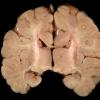

DEVELOPMENTAL MALFORMATIONS (11)